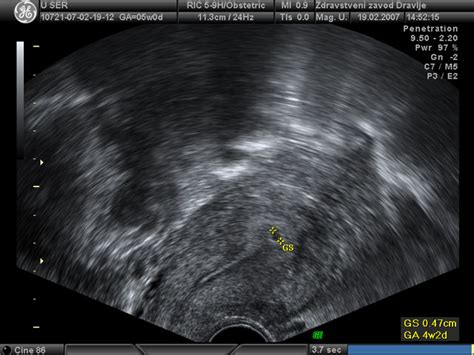

Ultrazvok v 4. tednu: Gestacijska vrečka kot prvi znak

V 4. tednu nosečnosti, ki sovpada s časom, ko bi sicer nastopila menstruacija, ultrazvok lahko pokaže prvi vidni znak nosečnosti - gestacijsko vrečko. Ta votla, zaobljena struktura se nahaja znotraj maternične sluznice in predstavlja zgodnje okolje, v katerem se bo razvijal zarodek. Velikost in oblika gestacijske vrečke sta ključna kazalnika zgodnjega razvoja.

Po podatkih iz medicinskih virov in forumov se gestacijska vrečka prvič pojavi okoli 4. tedna gestacijske starosti, ko njena velikost običajno znaša med 2 do 3 mm. Ta struktura nato narašča s hitrostjo približno 1 mm na dan do okoli 9. tedna nosečnosti. V 4. tednu nosečnosti je velikost gestacijske vrečke še majhna, kar ustreza obdobju tik ob izostanku menstruacije ali v prvih dneh po njem. Vendar je pomembno poudariti, da so lahko odstopanja povsem normalna, saj lahko zgodnejša ali poznejša oploditev vpliva na velikost strukture.

V nekaterih primerih, kot je bilo omenjeno na forumih, je lahko velikost gestacijske vrečke nekoliko večja od pričakovane, kar je lahko povezano z večjo gestacijsko starostjo ali drugimi dejavniki. V primeru dvojčkov, na primer, je možno, da se vidita dve gestacijski vrečki, kar lahko vpliva na skupno velikost ali videz ultrazvočne slike. Ključno je, da velikost gestacijske vrečke sovpada s pričakovano gestacijsko starostjo, saj lahko večja odstopanja zahtevajo dodatno spremljanje.